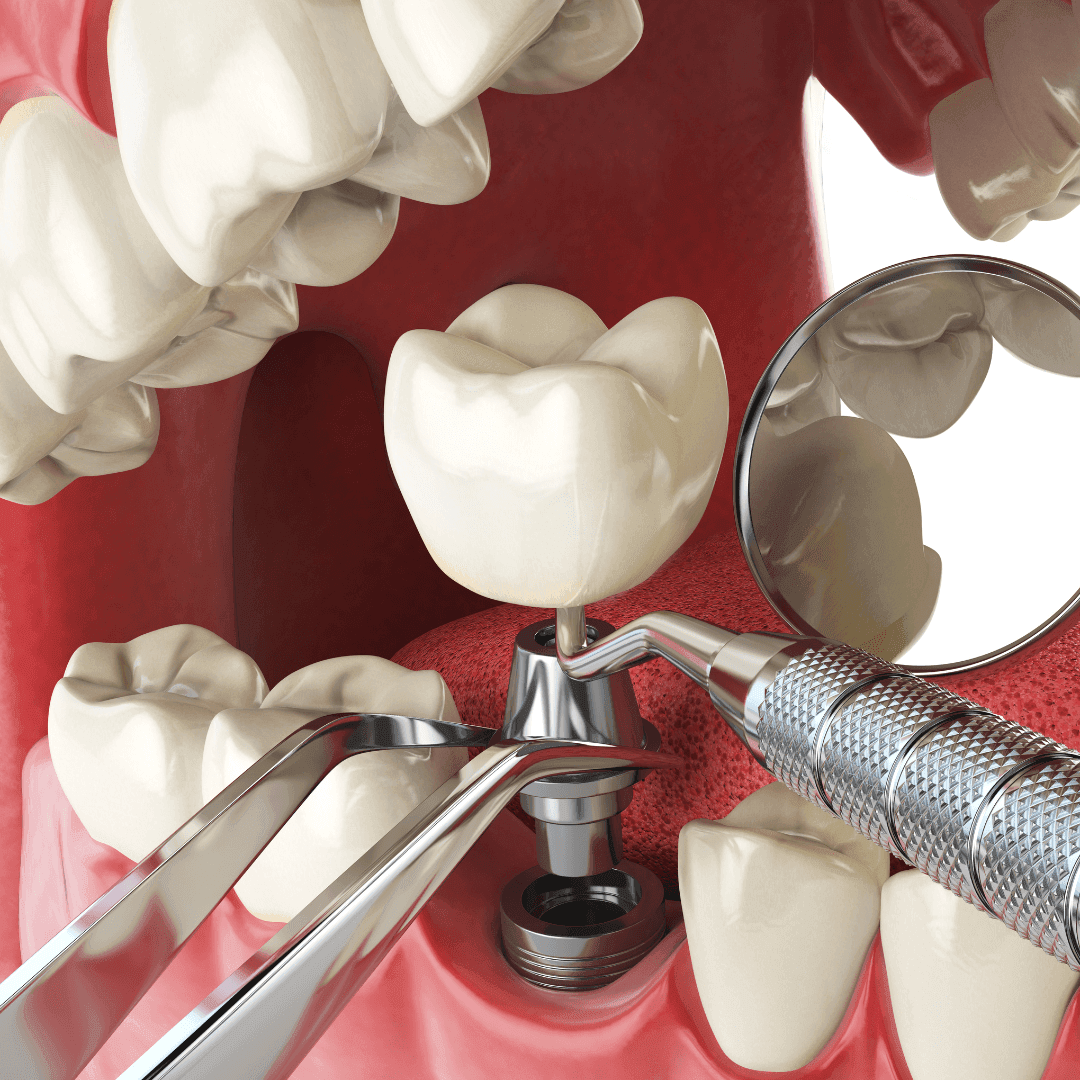

Zubni implanti su najsavremenije rešenje za trajnu nadoknadu jednog, više ili svih zuba.

Reč je o titanijumskim nosačima koji zamenjuju koren zuba. Na njih se postavlja protetska nadoknada (krunica) koja u potpunosti imitira prirodan zub – izgledom, funkcijom i osećajem.

Proces ugradnje implantata u Magic Dent ordinaciji obuhvata tri ključne faze:

3D snimanje vilice i detaljan pregled. Sve u našoj ordinaciji.

Bezbolno postavljanje implantata u kost pod lokalnom anestezijom.

Nakon zarastanja, precizno uzimamo otisak pomoću intraoralnog skenera i izrađujemo krunice koje se savršeno uklapaju.